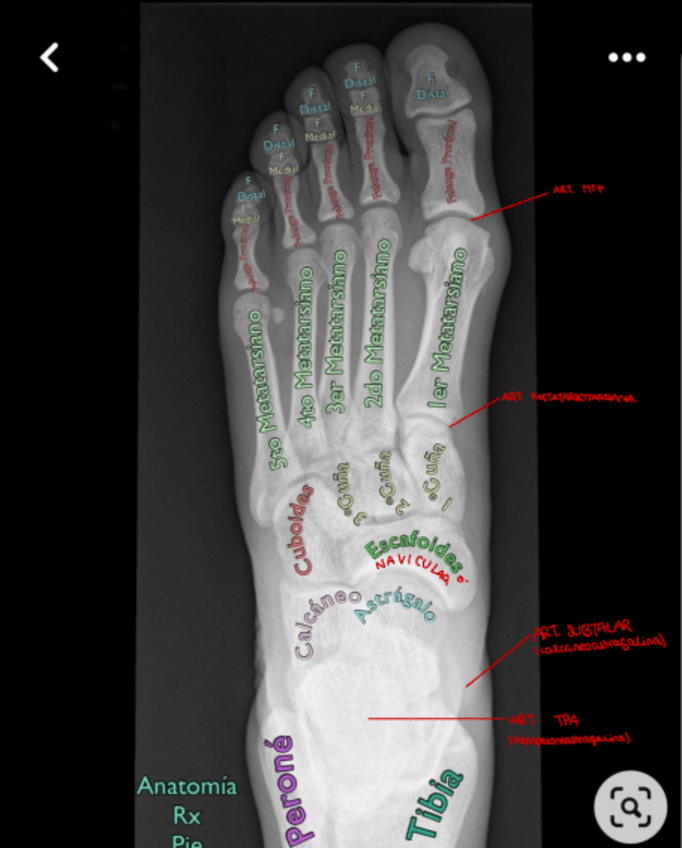

Pie, tobillo, rodilla y cadera